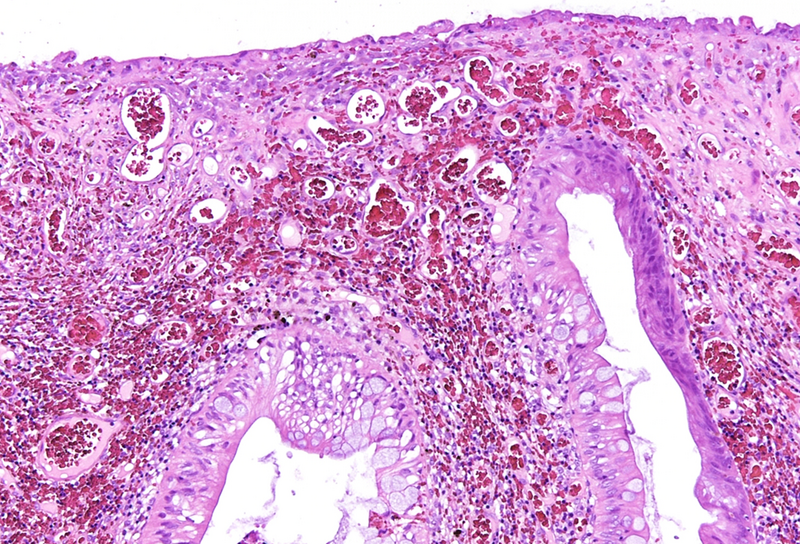

Histologically, the lesion exhibited a complex lobulated architecture (Panel A), with central cores of ramifying bands of smooth muscle extending from the muscularis mucosae into the lamina propria, configuring an arborizing pattern (Panel B). The epithelium exhibited neither cytologic nor architectural atypia and was regarded as reactive (non-dysplastic), with some glands showing dilation and distortion (Panel C). Recovering epithelium was observed on the surface, together with granulation tissue (Panel D).

Notably, the lesion demonstrated beginning pseudo-invasion, defined by the presence of misplaced benign glandular elements extending into the upper part of the stalk. There was mild inflammation of the lamina propria, abundant hemorrhage and hemosiderin-laden macrophages were also observed (Panels E-F). Immunohistochemistry for desmin and smooth muscle actin (SMA) was performed to highlight the smooth muscle fibers (compare Panel B) and emphasize the typical lobulated and arborizing architecture of this type of polyp.